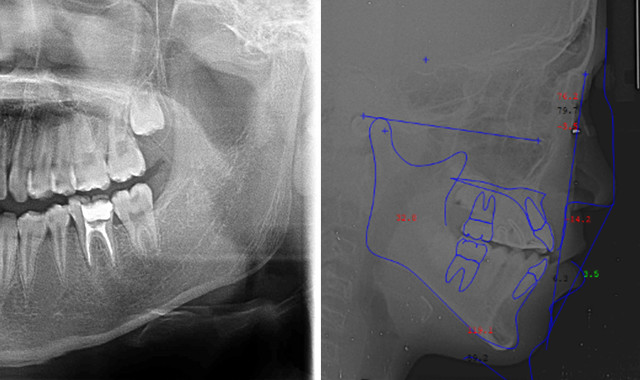

マウスピース型矯正装置作製のために、歯型を採得します。また、診断に必要なデータを揃えるため、顔貌や口腔内の写真撮影、パノラマレントゲン写真、頭部X線規格写真、虫歯・歯周病の検査なども行います。

3.診断と治療計画の説明

精密検査の結果から、3次元シミュレーションソフトを用いて治療完了までの総合的な治療計画を立て、ご提案させていただきます。